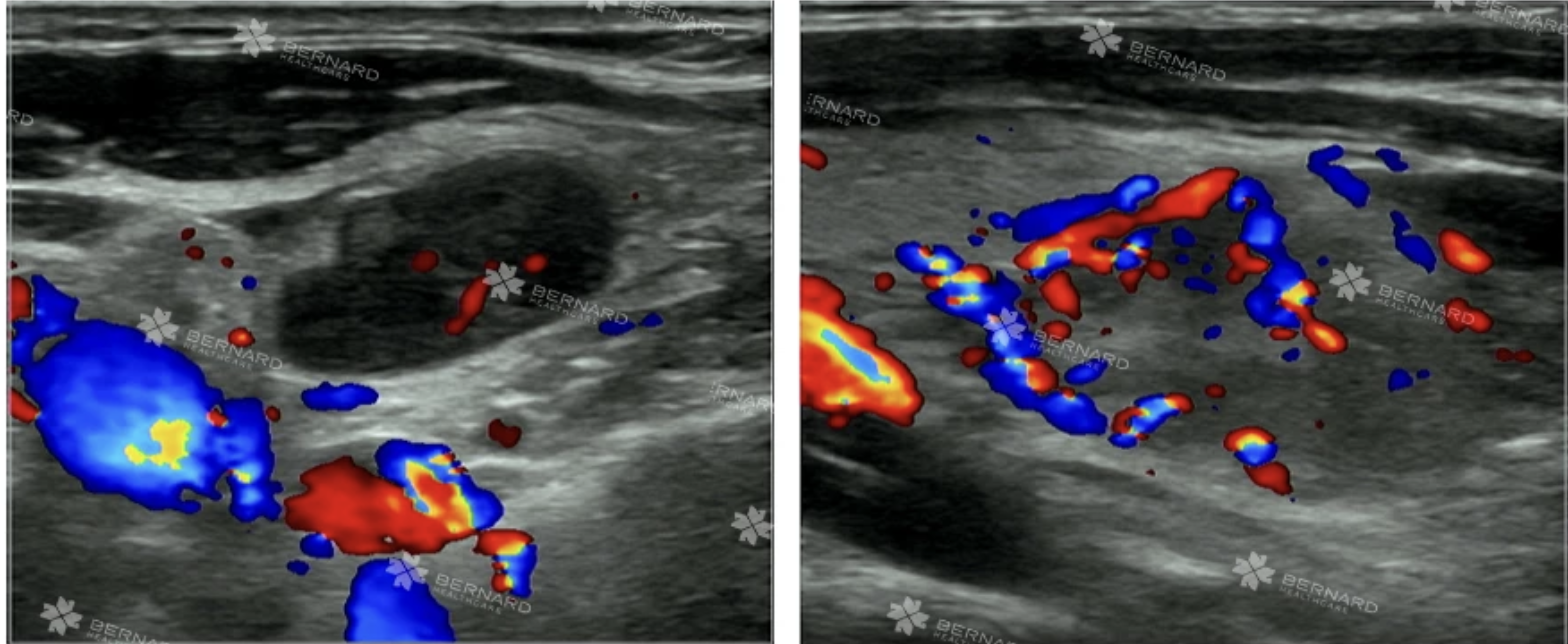

Hình ảnh siêu âm cho thấy nhiều hạch bất thường ở cả vùng cổ và nách: Một số hạch có đặc điểm lành tính, giới hạn rõ, bờ đều, còn rốn hạch. Tuy nhiên, tại vùng cổ trái, có hạch echo kém, tăng tưới máu rốn hạch, bên trong xuất hiện vùng hoại tử - dấu hiệu đáng lo ngại.

Ngoài ra, siêu âm nách trái cũng phát hiện hạch có hình ảnh không điển hình. Các dữ kiện này khiến bác sĩ nghi ngờ lao hạch, nhưng cũng không loại trừ khả năng lymphoma - một dạng ung thư hạch bạch huyết.